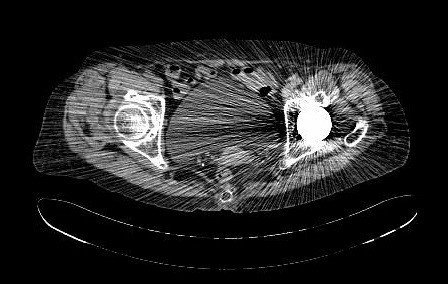

查体:专科:左髋部后外侧陈旧手术瘢痕,左髋关节前方压痛、无轴向叩击痛阴性,无大转子叩击痛,双下肢感觉及血运均正常。双下肢肌力V级。动量:右髋内外旋诱发疼痛,屈曲90度疼痛。外旋明显滚动试验阴性,左髋4字试验阳性。双下肢等长。左髋关节屈90°,伸0°,外展40°,内收20°,内旋30°外旋10°。右髋关节屈120°,伸直0°,外展40°,内收20°,内旋30°外旋30°。 辅助检查:2010-12-08 ESR 6.0mm/h,2011-01-04外院CRP8.5mg/l(参考范围0-10mg/l)X线示左双动股骨头置换术后,假体松动、下沉,髓腔内可见骨水泥影。近端干骺端骨质明显缺损。髓腔内侧皮质形态不规则。

诊断:左双动股骨头置换术后假体松动、下沉、股骨骨缺损(PaproskyII型) 治疗:患者在全麻下左双动股骨头假体取出+同种异体骨植骨+左全髋关节翻修术,术后予以抗炎(二联)+抗凝+镇痛+护胃+补液等治疗,并予以抗骨质疏松药物